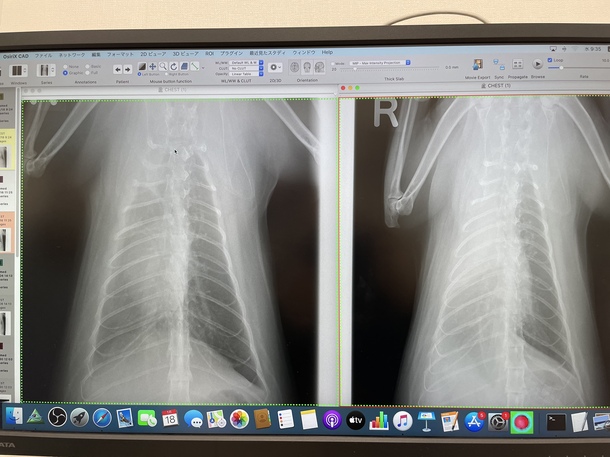

見てください!!!

肺の曇りがだいぶん消えて心臓の影がうっすら見えるようになりました!

これで一度薬をやめてみて、悪化しなかったら投薬は終了です!